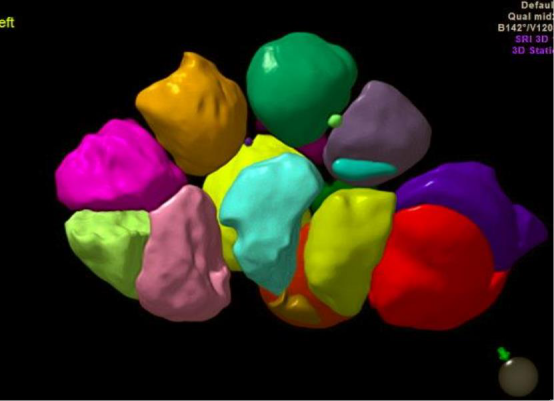

卵巢内按大小分别标记为不同的颜色,可直观观察卵泡的个数和大小。